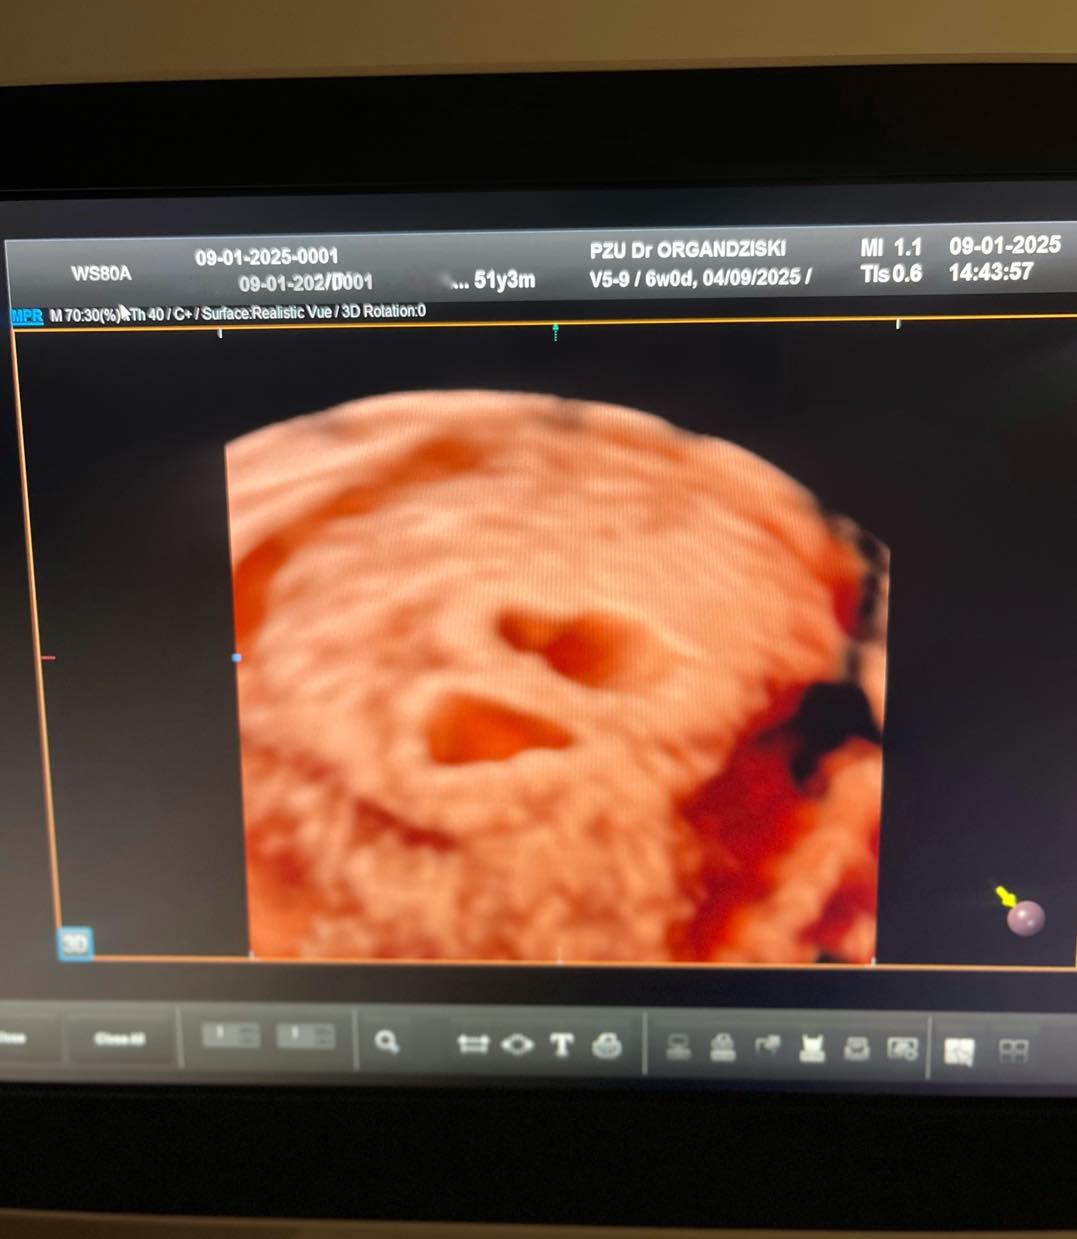

Годините се само бројка за исполнување на сонот! Не постојат препреки за нашиот тим од ИВФ Одделот и пишуваме уште еден голем успех!

Пациентката има две неуспешни ин витро процедури во други клиники, една со сопствени и една со донирани ооцити.

Во нашата болница постигнавме бременост со алогенеичко БПО со два ембриони!